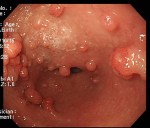

[Left] Polyps in the colon. [Right] Cancer in the Colon/Rectum area.

Cleo had her endoscopy and colonoscopy done after the Chinese New Year of 2017. The doctor didn’t find ulcers or parasites. They found some nodules in parts of her colon and rectum. A such, they did a biopsy on some of those abnormal tissue and sent those to the labs for examination.

Imagine the shock Cleo had when her doctor called her and her husband in for an urgent discussion. He revealed that the tissue were an aggressive malignant tumour that has penetrated the sub-mucosa and affected a large section of her colon and rectum. He recommended immediate surgery before it spread further and penetrate deeper!